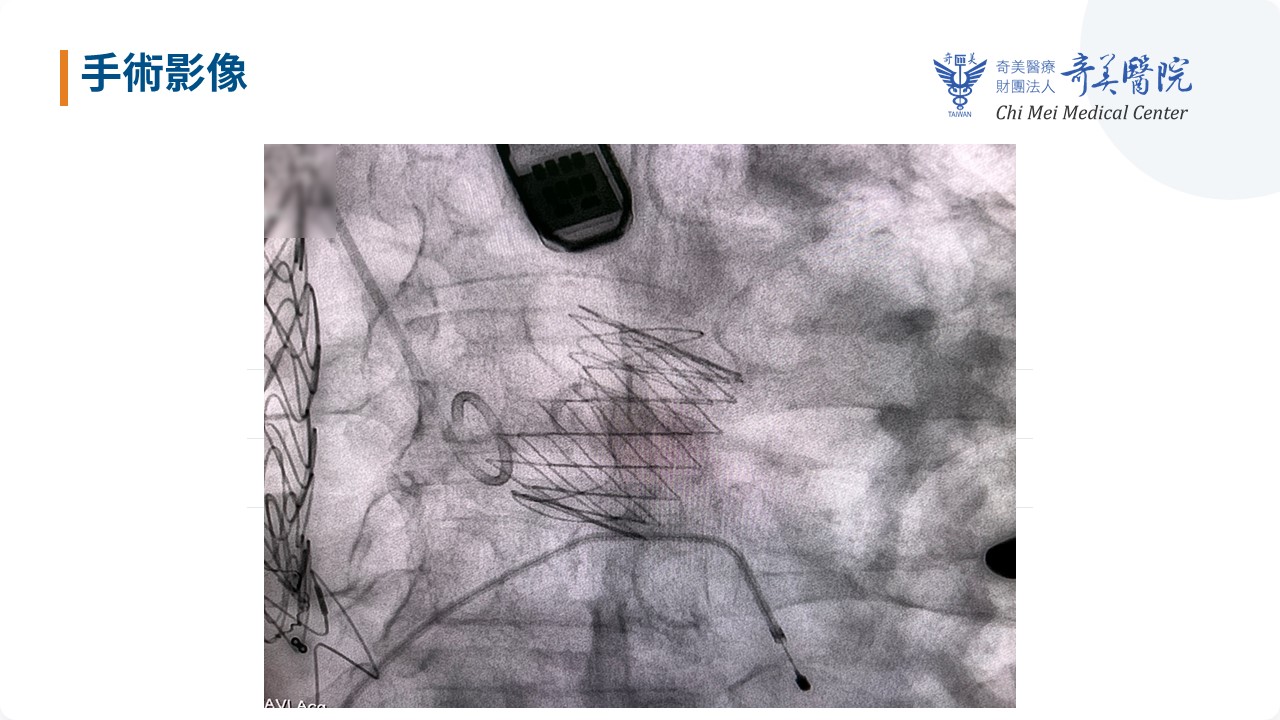

奇美醫療財團法人奇美醫院心臟血管外科主任吳南鈞、主治醫師李政亞與心臟血管內科主任施志遠、主治醫師涂冠杰共同帶領團隊,114年12月9日於南部率先成功完成「經心尖(Transapical)經導管主動脈瓣膜置換術(TAVI)」使用新型瓣膜裝置治療「純重度主動脈瓣逆流(AR)」的高難度個案。由於病人嚴重瓣膜逆流導致心臟負荷加重,且合併多重複雜主動脈解剖與既往主動脈介入手術史,考量傳統正中開胸外科主動脈瓣置換(Surgical AVR)風險極高,團隊改採經心尖微創路徑成功完成瓣膜置換,術後恢復良好,8天即順利出院,充分展現奇美醫院在高難度結構性心臟病治療上與跨科整合照護的能力,即使是解剖複雜、風險極高的病人,也能獲得最安全、最適合的治療。

成功案例柯先生採用經心尖(Transapical)的經導管主動脈瓣膜置換術(TAVI)(圖-奇美醫院提供)